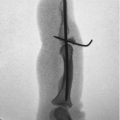

34 Fixation of Uni and Bicondylar Phalangeal Fractures

34.1 Description

Condyle fractures are intra-articular fractures involving the distal aspect of the proximal and middle phalanx. The majority of condyle fractures tend to be inherently unstable, even if nondisplaced initially. 1 Management of these injuries must account for the unique architecture of this joint, as it is not a simple hinge. The condyles of the proximal and middle phalanx have smaller radii of curvature compared with the concave base of the middle phalanx, providing motion with 4 degrees of freedom. 2 3 The structure of this joint provides mobility, stability, and circulation of synovial fluid. These relationships are lost with intra-articular and comminuted fractures, which must be repaired or reconstructed to restore normal function.